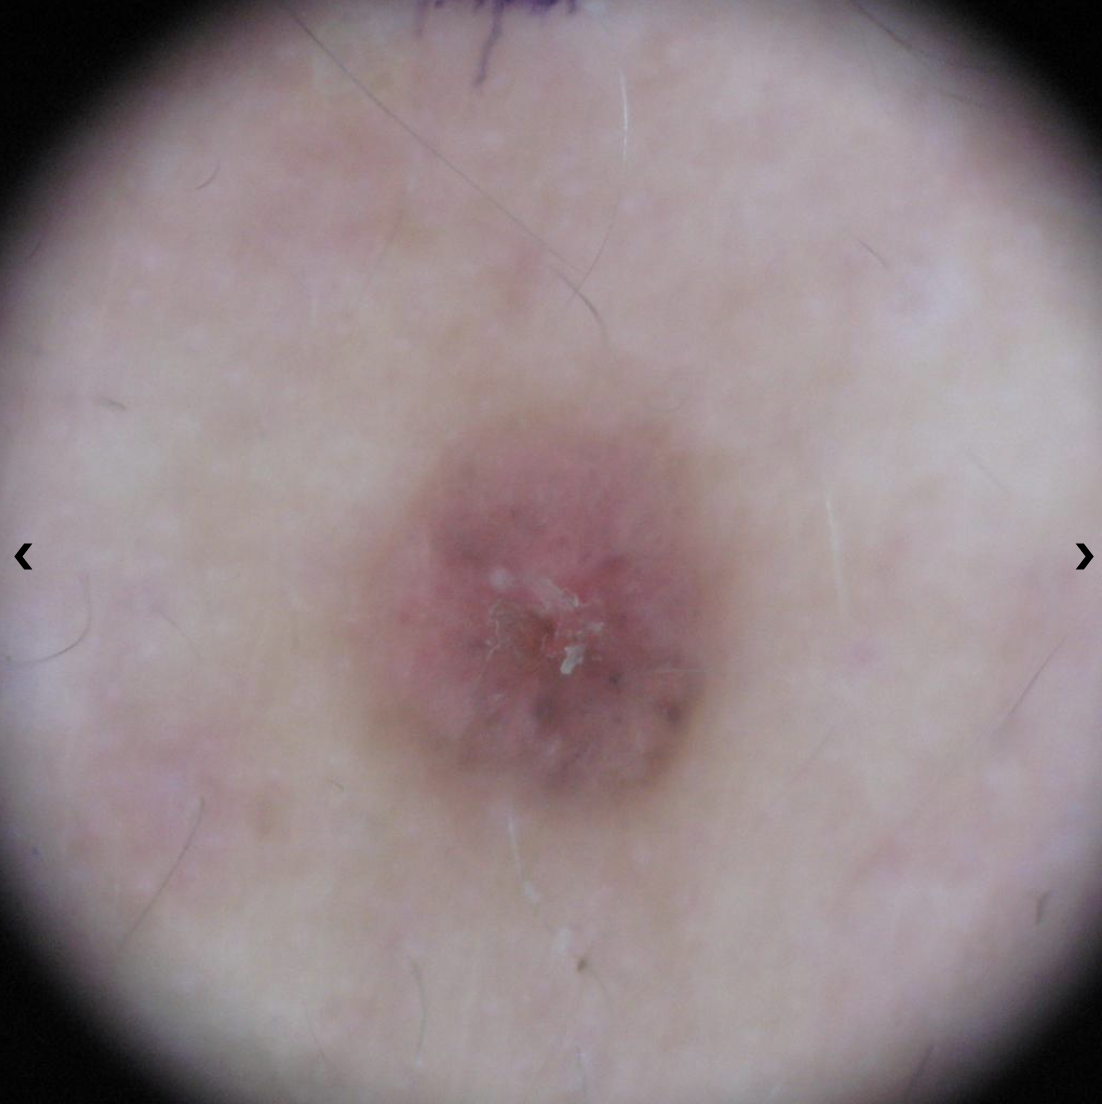

Melanoma Photos

Nodular melanoma on the leg of a Native American woman.

Photo: International Skin Imaging Collaboration

Amelanotic melanomas may be pinkish-looking, reddish, purple, normal skin color or essentially clear and colorless.